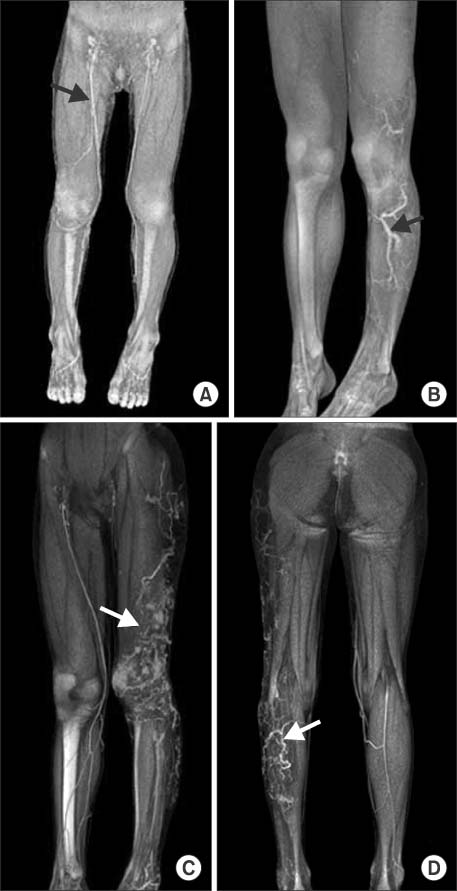

Fig. 1

(A) A 3-year-old child has dilatation of the right great saphenous vein (arrow). (B) A 15-year-old child has enlargement of great and small saphenous vein (arrow). (C, D) A 7-year-old child has venous malformation of left lower leg (arrow). She has prominent venous dilatation of the thigh and knee portion (arrow).

Fig. 1 (A) A 3-year-old child has dilatation of the right great saphenous vein (arrow). (B) A 15-year-old child has enlargement of great and small saphenous vein (arrow). (C, D) A 7-year-old child has venous malformation of left lower leg (arrow). She has prominent venous dilatation of the thigh and knee portion (arrow).